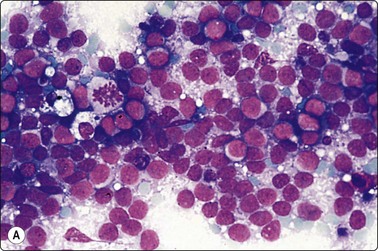

image

Fig. 5.1 Lymphoid globules

Numerous spherical fragments of blue cytoplasm of variable sizes dispersed between the lymphoid cells; some nuclear fragments. Large cell lymphoma of tonsil (MGG, HP).